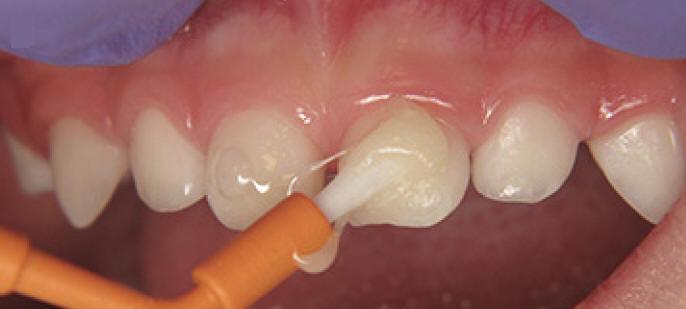

Técnica de aplicación profesional de un agente remineralizante del esmalte y dentina (Mi Paste)

1. Siguiendo la rutina de profilaxis para remover la placa, restos de comida o manchas, pida al paciente que se enjuague la boca.

2. Aplique una generosa capa de MI Paste como parte del terminado final en la superficie de los dientes, utilizando una copa profiláctica ó un cepillo profiláctico. En áreas de difícil acceso use un cepillo inter proximal.

3. Indique al paciente que mantenga el producto MI Paste por lo más que pueda en su boca (1-2 minutos o más) sin  escupir o tragar el producto. Entre más tiempo se mantenga MI Paste en contacto con los dientes, más efectivo será el resultado.

4. Pida al paciente no comer o beber nada en los siguientes 30 minutos después del tratamiento.

Nota: mi paste es usado para remineralizar lesiones iniciales de esmalte, dentina y cemento. También para disminuir la sensibilidad en la unión cemento esmalte (UCE)